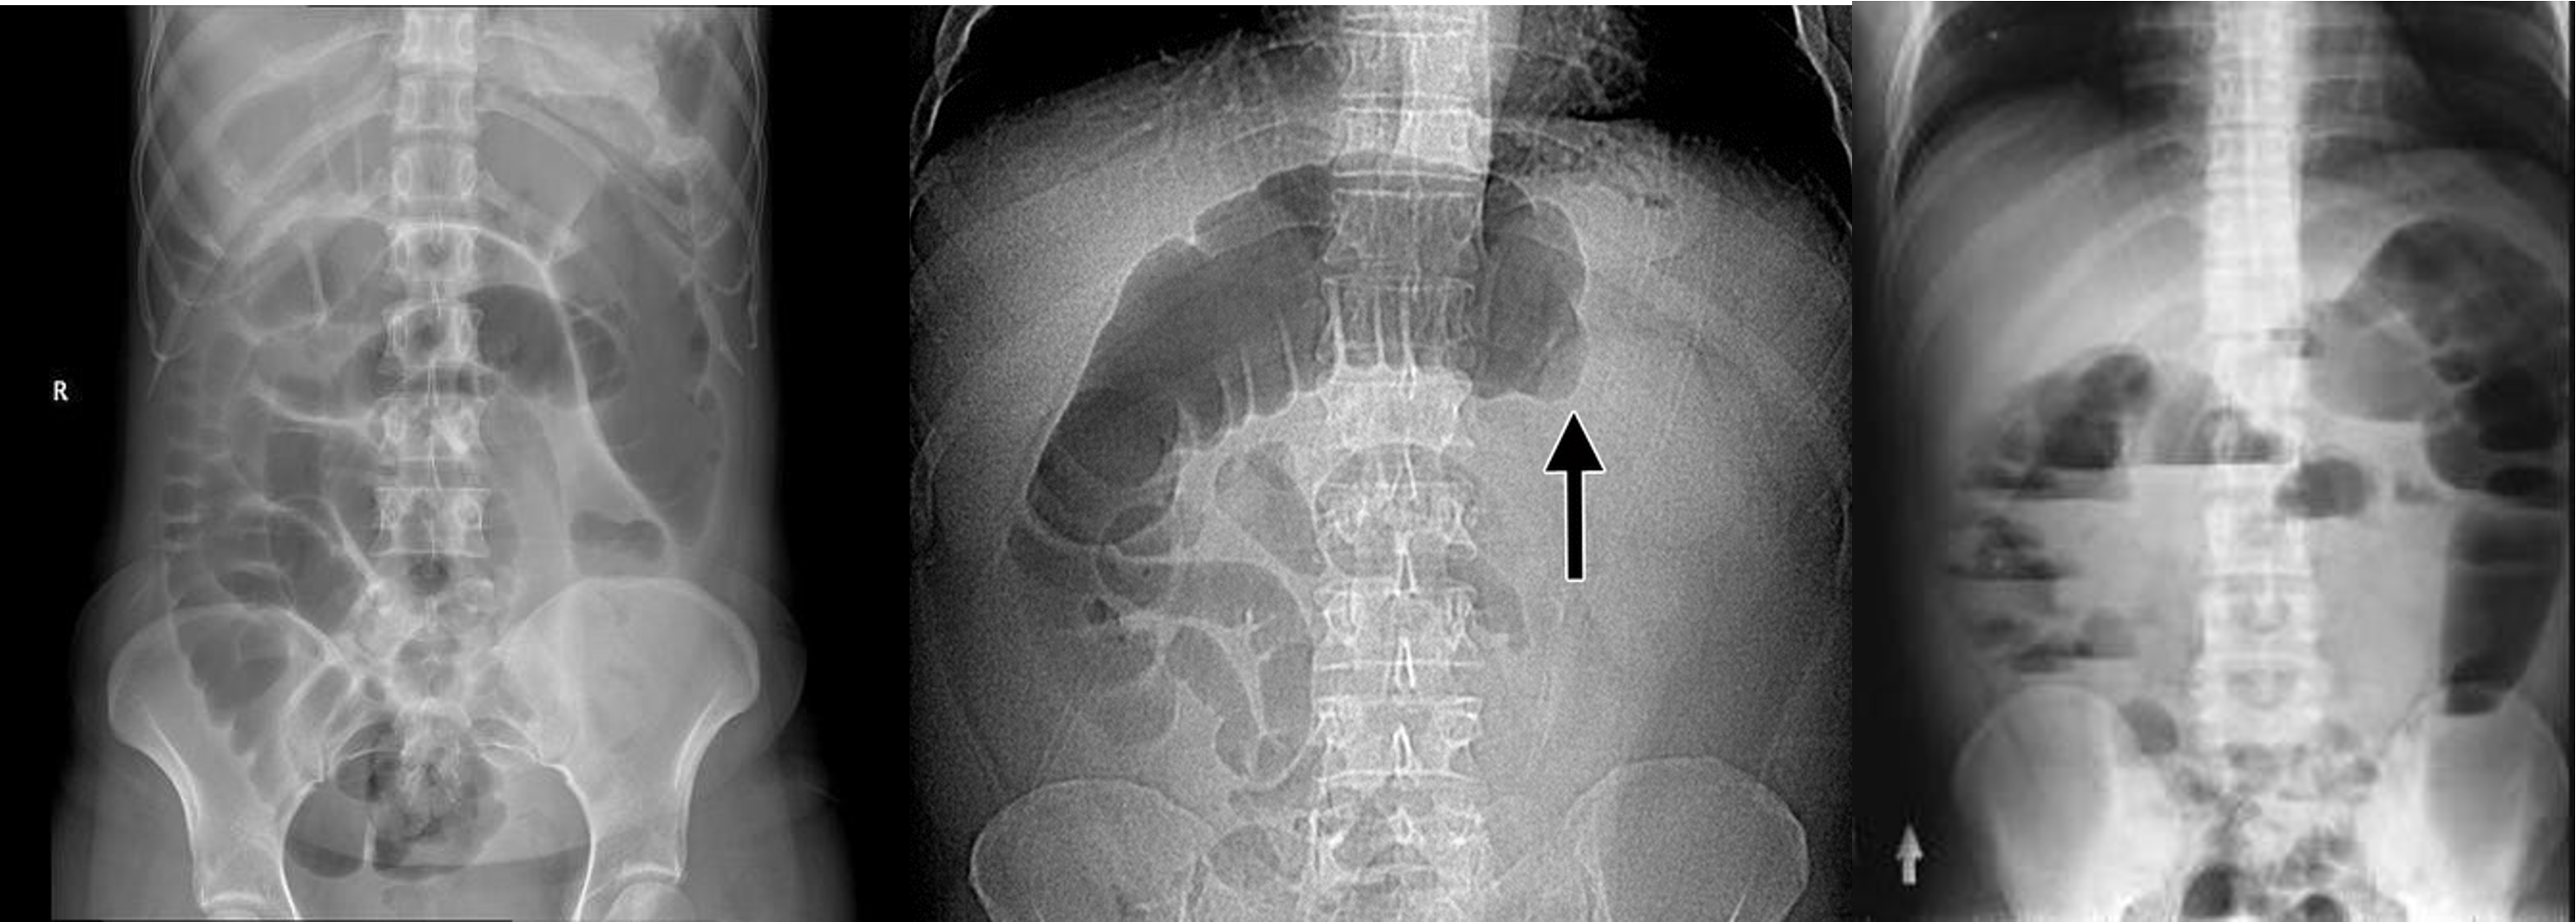

2) Dilated bowel (diff; cancer colon) -

closed loop obstruction from both sides result large bowel most dangerous left side most common cancers

- coffe bean - omega sign - volvulus twisting around its axis - it is closed loop obstruction very dangerous - (treat clonoscopy decompression)

- volvulus

- abdominal x-ray - Dilated colon (diff - cancer colon, ulcerative colittis)

- 8 air fluid - small intestinal central - intistinal obstruction due adhesion - stack of coins. ++ NG tube aspiration relieve from vomitting

- dilated small bowel obstruction - stack of coins